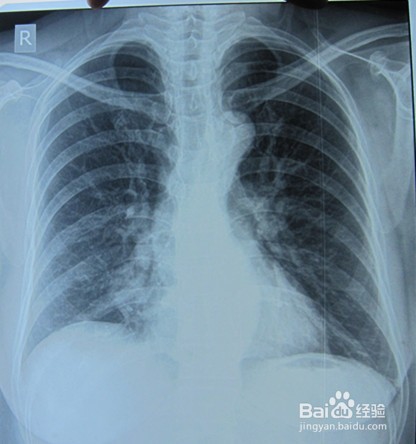

肺炎是一种儿童比较容易得的疾病,而且在春秋这两季节更容易得病,而且得这个病的儿童的死亡率也是比较高的,肺炎刚开始的症状就是感冒,而且还可能会伴有其他的症状,呼吸会见快,并且还是会喘的,有种窒息的感觉,呼吸明显比平时费力,后来就会有发烧的情况,高烧不退,咳嗽会加剧。

得肺炎的人,呼吸就比较困难,因此就需要多呼吸新鲜的空气,也需要多休息,多喝水,患者的痰也是比较多的,这样很不利于呼吸的,因此可以适当的吃一些可以化痰止咳的一些事物,这样比较不容易恶化病情,当然最重要的还是要抗感染的,一些外部细菌的感染,如果是细菌性肺炎的治疗,患者可以根据痰培养和药物敏感试验结果,选择体外试验敏感的抗菌药物,但是这主要还是要根据患者的年龄,程度的好坏决定,不能乱吃药的。

如果怀疑是肺炎的话就应该马上注射抗菌药物,这种病是急性的,不能够拖延的,等到病情稳定后,这时就可以将静脉途径改为口服治疗,但是肺炎抗菌药物疗程至少5天,这样才有用,大部分患者可能需要的是7天,甚至是更久的,这个就视个人情况而定了,当自己的体温正常48~72小时,无肺炎任何一项临床不稳定征象可停用抗菌药物。

支气管肺炎呢,如果是一般的治疗的话,就要保持,患者所住环境的干净卫生,还要确保环境的湿度,不宜太干,温度也要控制好,20度左右最好,也要保持室内的空气新鲜,及时的通风换气,保持空气的流通,饮食方面也要维持足够的量,多吃一些流食,像牛乳,米汤,果汁,也要多补充一些维生素A,B,C,D,注意加强营养,防止营养不良。